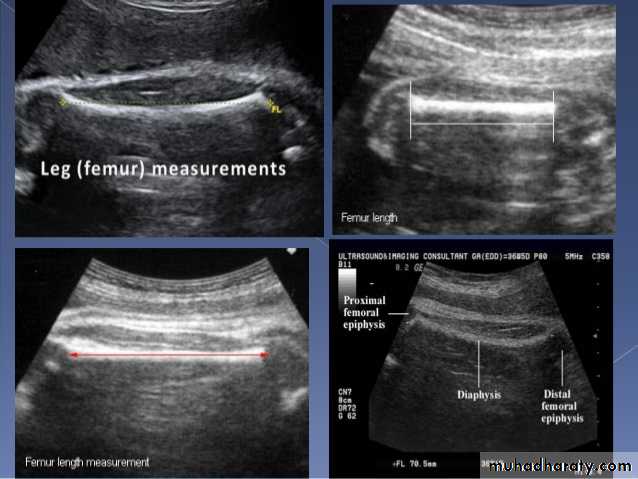

Mosul Medical College /radiology department2016BPD together with head circumference (HC), abdominal circumference (AC), and femur length (FL) are computed to produce an estimate of fetal weight. In the second trimester this may be extrapolated to an estimate of gestational age and an estimated due date (EDD) .